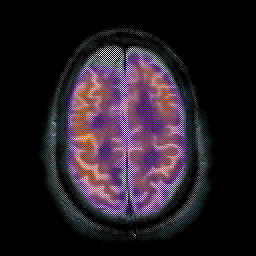

Subacute Stroke overlay -- Slice #18

[Home][Help][Clinical] Slice 18